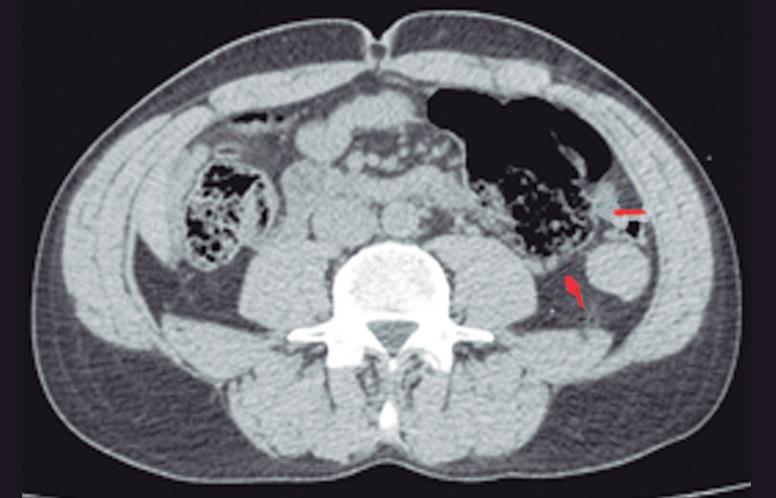

El páncreas anular en neonatos, cuando es sintomático, provoca síndrome de obstrucción gástrica, clínicamente manifestado con vómitos como consecuencia de la compresión y estenosis de la 2° porción duodenal. En los adultos también puede originar obstrucción gastrointestinal, y los pacientes presentan dolor abdominal, habitualmente postprandial y/o vómitos. En menor medida puede predisponer a PAR o bien a

Más allá del diagnóstico de esta anomalía debemos buscar signos imagenológicos indirectos de obstrucción gastrointestinal, como son la dilatación gástrica y de la 1° porción duodenal (Figura 10), con estrechez de la luz del duodeno en el sitio por donde transcurre a través del páncreas anular.18,19

A) Tomografía computada con contraste, plano coronal. El páncreas anular (flecha) provoca dilatación de la 1° porción del duodeno (cabezas de flecha). B) Tomografía computada con contraste, plano axial. Flechas: páncreas anular. Cabeza de flecha: duodeno. C) Tomografía computada con contraste, plano axial, corte más caudal que el previo. Flechas: páncreas anular.